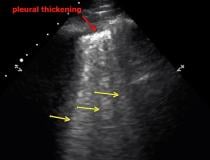

This photo gallery shows the variety of radiological presentations of COVID-19 (SARS-CoV-2) in medical imaging, including computed tomography (CT), radiograph X-rays, ultrasound, echocardiograms and magnetic resonance imaging (MRI). The radiology images show examples of typical COVID pneumonia in the lungs and the numerous complications the virus causes in the body in multiple organs, including the brain, kidneys, heart, abdomen and vascular system.

Ultrasound, especially hand-held ultrasound imaging devices, have become a primary imaging modality for novel coronavirus because of the ease to bag the device and sterilize it after use. CT and mobile X-ray systems are also used as front-line imaging systems for COVID-positive or suspected COVID patients.